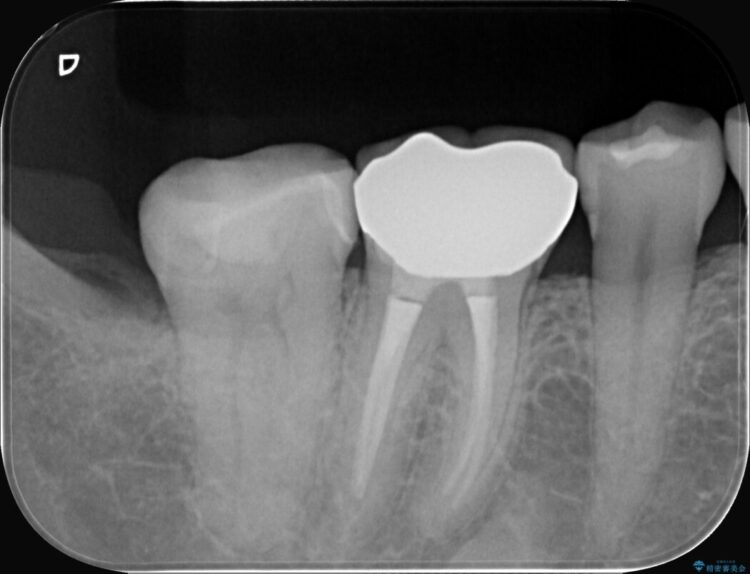

診査の結果、右下7番目の歯の奥側の面や手前の歯との間にう蝕があり、噛む面にも蝕処置によるレジン材料が詰まっていました。

う蝕、古い材料を全て除去し、セラミックインレーでやり替えることとしました。